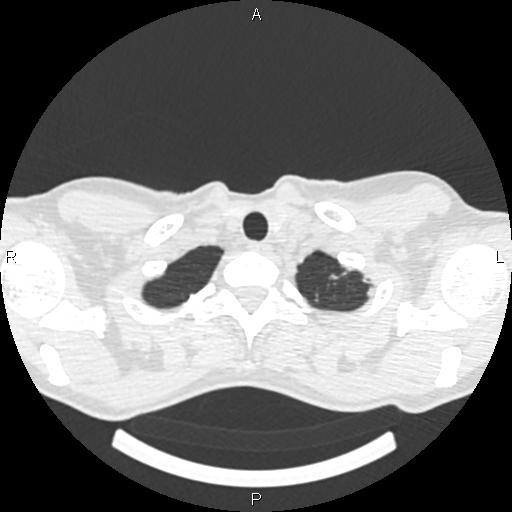

Женщина, 1975 г.р. ВИЧ инфицирована. Жалобы неспецифичны: легкое покашливание (иногда), легкое похудение. Температуры нет. Первое КТ сделано ровно 4 мес назад. Отмечались множественные...

Тип: Клиническое наблюдение

Область: Грудная клетка и верхние дыхательные пути

Модальность: КТ

Дата: 01.06.2016 - 20:47